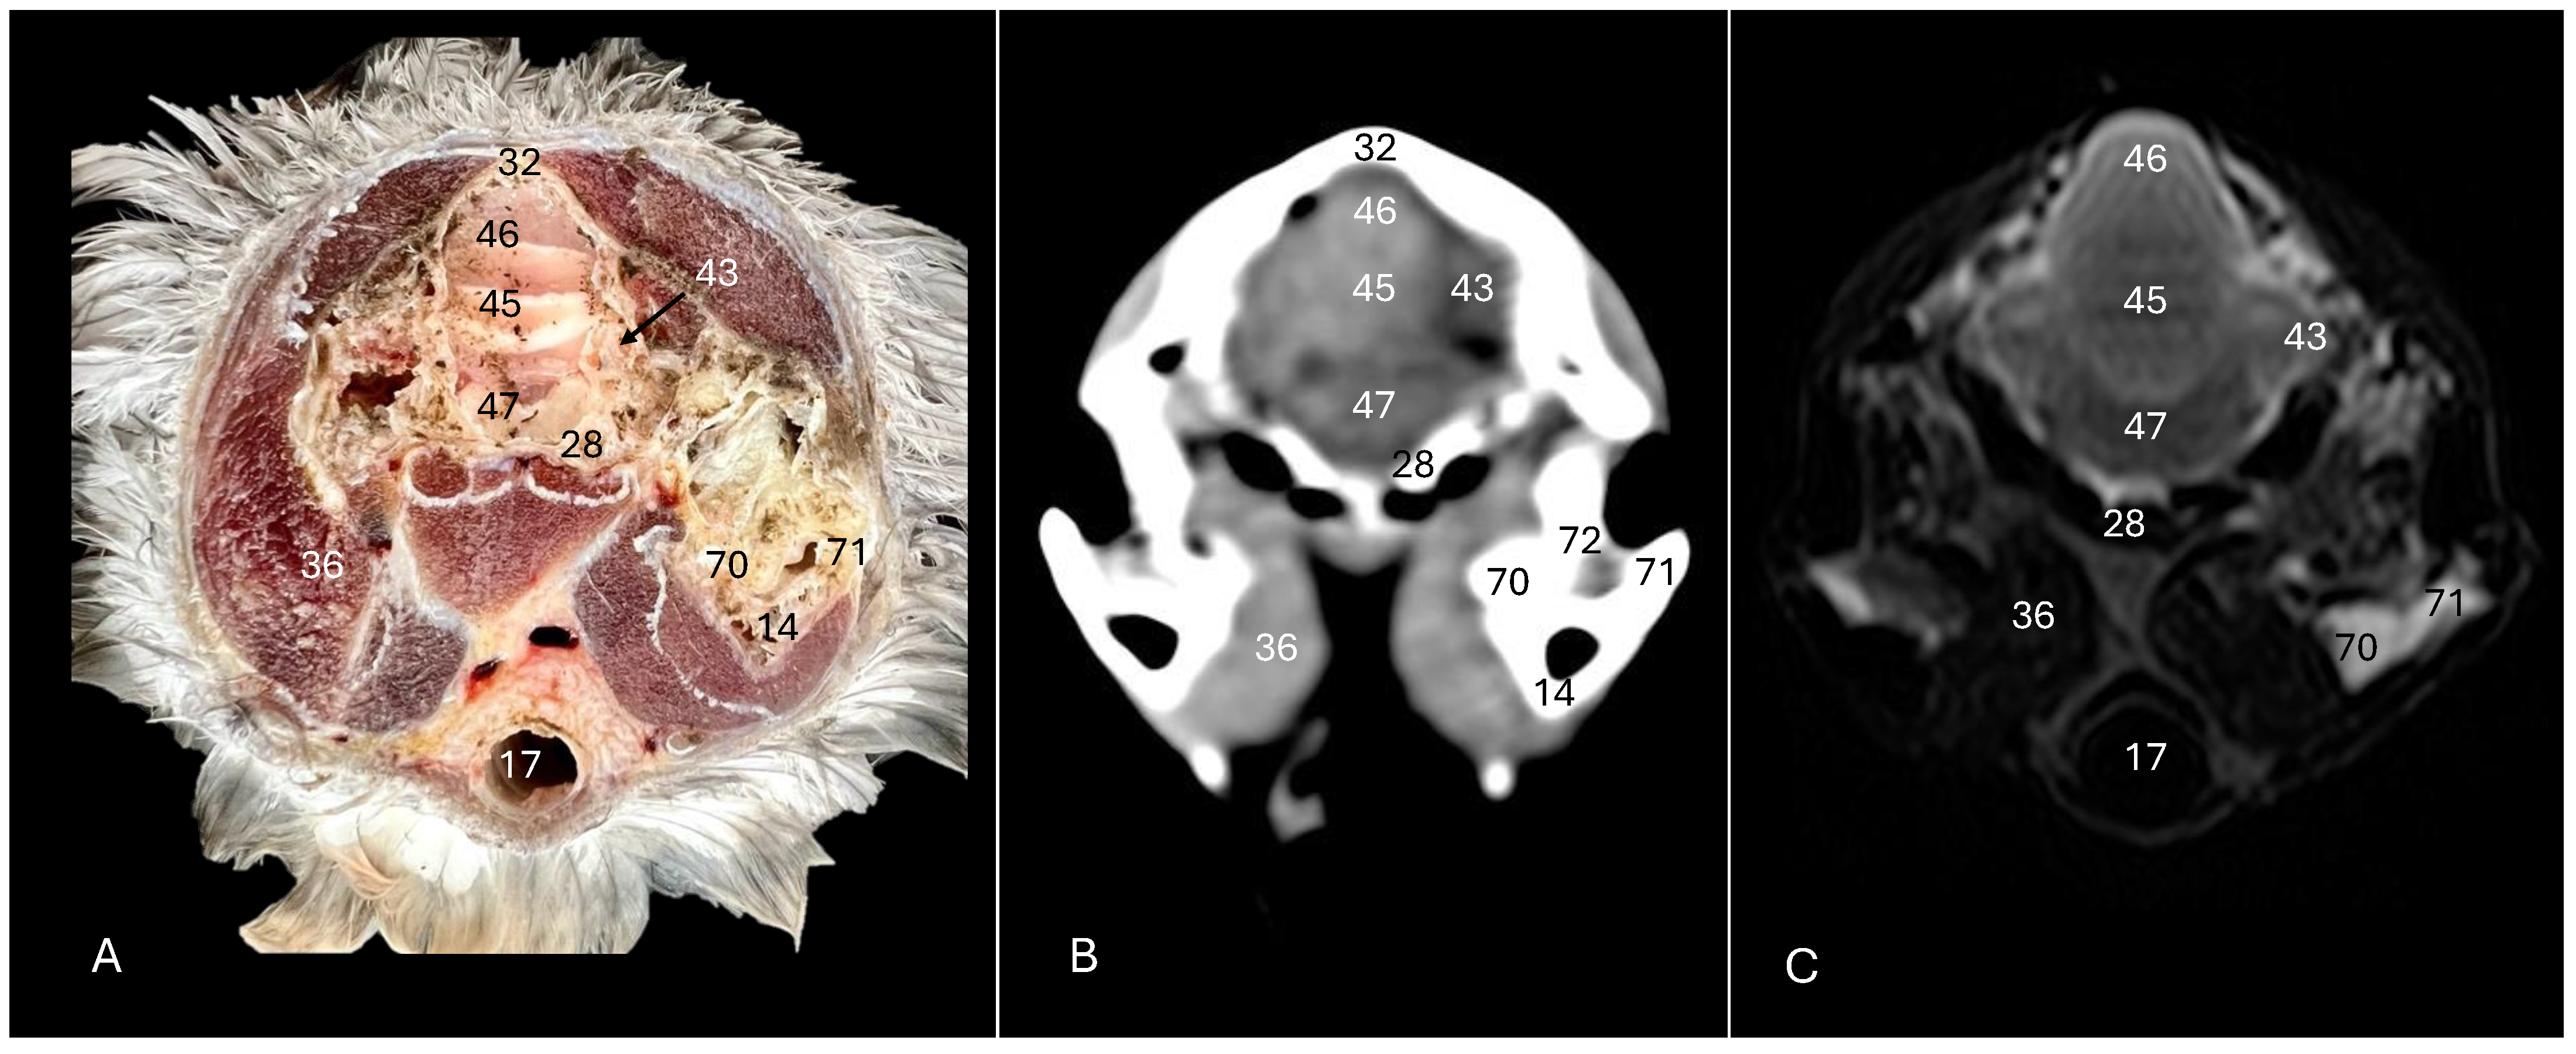

Figure 5. Anatomical cross-section (A), soft tissue CT window (B) and T2-weighted MR (C) transverse images of the Cory’s shearwater head at the level of the cerebellum, corresponding to line IV in Figure 1. 14: Mandible; 17: trachea; 28: basioccipital bone; 32: os parietale; 36: musculus depressor mandibulae pars superficialis plus musculus adductor mandibulae externus; 43: cerebellar hemisphere; 45: cerebellum (body); 46: folia of cerebellum; 47: pons; 70: medial process of the mandible; 71: lateral process of the mandible; 72: quadrate articular fossa.

Figure 6. Anatomical cross-section (A), soft tissue CT window (B) and T2-weighted MR (C) transverse images of the Cory’s shearwater head at the level of the caudal cerebellum, corresponding to line V in Figure 1. 17: Trachea; 26: middle ear; 28: basioccipital bone; 36: depressor mandibulae pars superficialis plus musculus adductor mandibulae externus; 45: cerebellum (body); 40: medulla oblongata; 52: os supraoccipitale; 70: medial process of the mandible; 71: lateral process of the mandible.

These sections also provided insights into other components of the Cory’s shearwater brain. Among these were the mesencephalon, the notable large corpus cerebelli, the internal medullary body characterized by an internal white substance, and caudally, the small paired cerebellar hemispheres, which were identified in the transverse and dorsal sections (illustrated as numbers 45, 80 and 43, respectively, in Figure 5A, Figure 6A, Figure 7A, Figure 8A, Figure 9A and Figure 10A). Additionally, these sections facilitated the identification of the ventral portion of the rhombencephalon, encompassing different components such as the pons and the medulla oblongata, which rested on the basioccipital bone (illustrated as numbers 47 and 40, respectively, in Figure 5A, Figure 6A and Figure 10A).

3.3. Magnetic Resonance Imaging (MRI)

No discernible anatomical differences were observed in the examined shearwaters; however, it is noteworthy that compared to CT, CNS structures were better visualized. Therefore, T2W MR images demonstrated precise alignment with the cranial structures observed in the cadaveric cross-sections, providing a comprehensive view of the CNS and its associated structures. Thus, the examination of Cory’s shearwater brains in transverse, dorsal and sagittal planes allowed the observation of the two telencephalic hemispheres, revealing regions of a moderate-intensity signal (labelled as number 16 in Figure 2C, Figure 3C, Figure 4C, Figure 7C, Figure 8C and Figure 10C). Notably, these imaging planes also facilitated the precise identification of the olfactory bulb, characterized by its small, tapering rostral structure, with moderate and uniform signal intensity (depicted as number 11 in Figure 2C, Figure 7C and Figure 10C). Moreover, the transverse T2W MR images displayed two curved dorsal structures with moderate signal intensity, corresponding with the hyperpallium (corresponding to number 21 in Figure 3C and Figure 4C). The diencephalon, another constituent of the forebrain, exhibited limited differentiation from the adjacent mesencephalon, displaying signals of moderate to low intensity (identified as numbers 49 and 57, respectively, in Figure 10C). Moreover, notable features of the mesencephalon, such as the optic lobe, were perfectly discernible in the transverse and dorsal T2-weighted MRI images, showcasing similar signal characteristics (represented as number 31 in Figure 4C and Figure 8C). Furthermore, other crucial components of the central nervous system, such as the pons and the medulla oblongata, were identifiable across transverse, dorsal and sagittal planes, and characterized by low-intensity signals (depicted as numbers 47 and 40, respectively, in Figure 5C, Figure 6C and Figure 10C). Adjacent to the brain stem, the corpus cerebellum and the small paired cerebellar hemispheres displayed indistinct areas of hypo- and moderate-intensity signals (shown as numbers 45 and 43, respectively, in Figure 5C, Figure 6C, Figure 7C, Figure 8C, Figure 9C and Figure 10C).